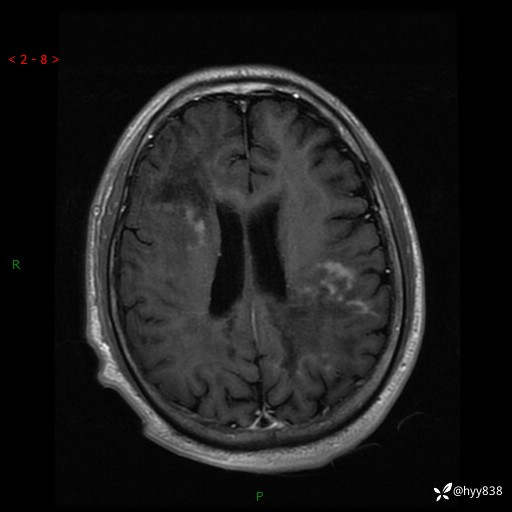

辅助检查:MRI

MRI T2WI

增强